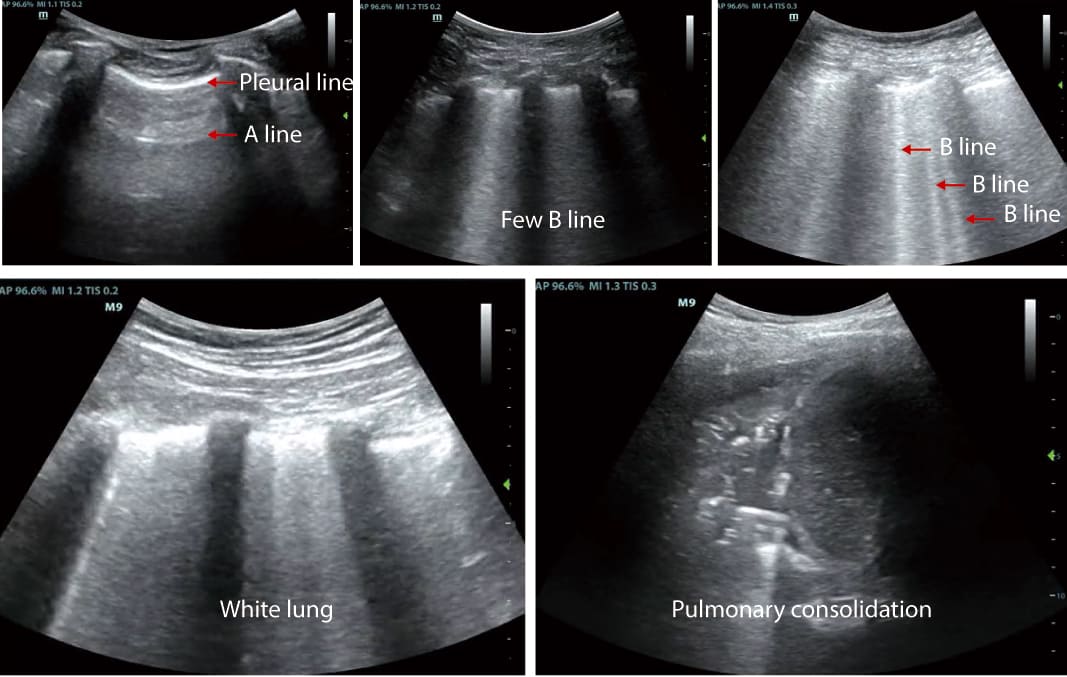

1. Professional Lung Examination Mode

The ability to observe changes in lung conditions is a game-changer for critical care clinicians. Portable ultrasound devices come equipped with a specialized lung examination mode that allows professionals to assess lung health with precision. This feature is particularly invaluable in cases where respiratory issues or acute conditions require immediate attention. It enables clinicians to visualize lung movement, detect abnormalities, and monitor changes in real-time.

Consider a scenario where a patient in the intensive care unit is experiencing respiratory distress. With a portable ultrasound device in hand, the clinician can immediately perform a lung examination, visualize lung movement, and identify any anomalies. This rapid assessment can be invaluable in diagnosing conditions like pneumothorax, pleural effusion, or atelectasis, allowing for swift interventions.